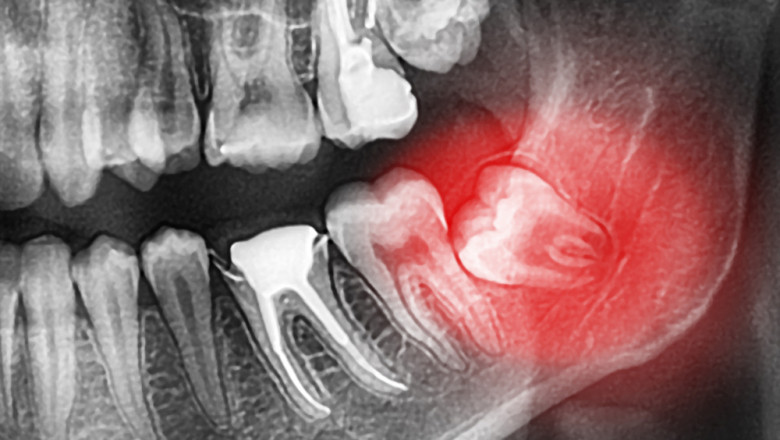

Dental Clinic Oral Surgery Sedation kwcdental 664 views Are you looking for oral surgery sedation? Visit https://www.kwcdental.com. At KWC Dental, for all surgical procedures, patients may discuss sedation options with a dentist. For more details, visit site. oral surgery sedation